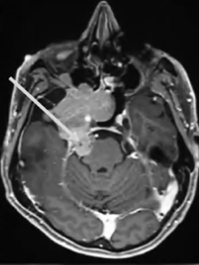

患者術(shù)前影像。(A)術(shù)前軸位T1加權(quán)釓增強(qiáng)磁共振成像(MRI),顯示腦膜瘤延伸至后顱窩、海綿竇、眼眶和蝶竇。(B)腫瘤延伸至中顱窩、翼腭窩和顳下窩。(C)術(shù)前軸位計(jì)算機(jī)斷層掃描(CT)顯示蝶骨大翼侵蝕和蝶竇受累。